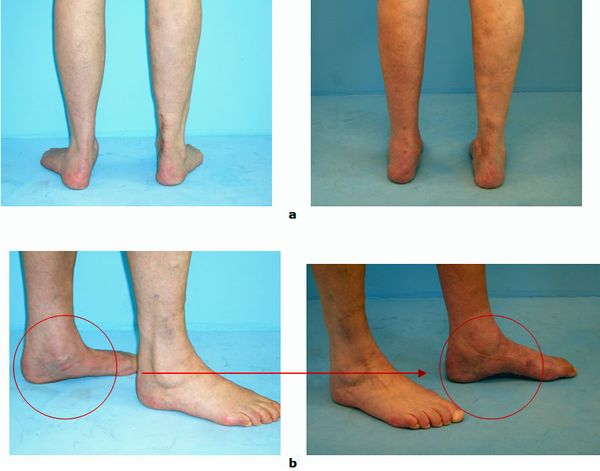

Abb.4: Gelenkerhaltende Korrektur eine Plattfußes durch Verschiebung des Fersenbeins (Calcaneusverschiebeosteotomie, Medial Slide Osteotomy), Fixierung des Knochens mir einer winkelstabilen Platte

Das Ziel ist eine gelenkerhaltende Therapie

Führen diese Maßnahmen nicht zum Erfolg, kommen operative Maßnahmen in Betracht. Diese sind im Stadium I die Entfernung oder das Spalten des Sehnenleitgewebes, im Stadium II wird durch eine Fersenbein Umstellung die mechanische Belastungsachse wieder hergestellt. Das Fersenbein wird bei diesem Eingriff um bis zu 15 mm verschoben und mit einer Spezialplatte fixiert (Calcaneusverschiebe osteotomie, Medial slide Osteotomy). Es handelt sich um verlässliche Operationen um die Fehlstellung dauerhaft zu beheben. Die Verschiebung führt zu einer Entlastung der tragenden Sehne und zu einer Korrektur der Rückfußfehlstellung. In gleicher Sitzung werden die überdehnten Weichteile an der Fußinnenseite gerafft und ggf. ein Sehnentransfer durchgeführt. Bei jungen Erwachsenen kann die Rekonstruktion auch durch eine Verlängerung des Fersenbeins (Evans Osteotomie) erfolgen. Die Fixierung erfolgt mit einer Schraube. Bei jugendlichen im Alter zwischen 10 und 15 Jahren ist häufig eine Aufrichtung ohne eine Knochendurchtrennung möglich. Das Verfahren wird als Arthrorise bezeichnet und kann minimalinvasiv durchgeführt werden. Leider quälen sich viele Patienten zu lange und kommen erst dann in die Fußsprechstunde wenn eine deutliche Bewegungseinschränkung und Arthrose im Mittel- und Rückfuß bereits eingetreten ist. In diesen Fällen (Stadium III und IV) können wir nur noch mit einer korrigierenden Arthrodese (Gelenkfusion) helfen. Die Patienten profitieren auch von diesem Eingriff insbesondere bzgl. der Schmerzsymptomatik erheblich, jedoch kann eine leichte Einschränkung beim Gehen verbleiben. Ein spezielles orthopädisches Schuhwerk ist in der Regel nicht notwendig.

Abb.5: a Korrektur des Plattfußes mit Beseitigung der Vorfußabweichung und

b Aufrichtung des Fußlängsgewölbes